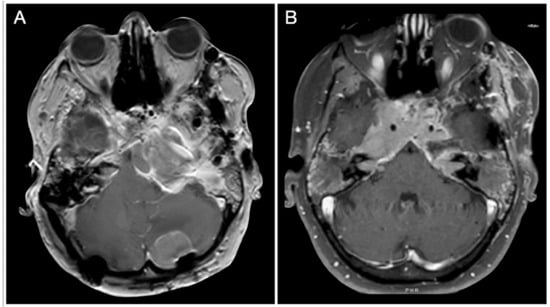

3.3.1. Case #4: Involvement of the Middle Skull Base with Parenchymal Invasion